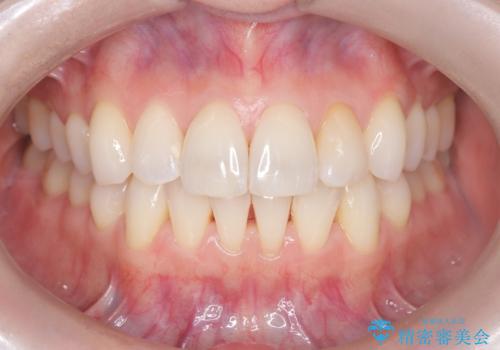

矯正後の後戻りで前歯にガタツキができてしまった インビザラインで改善

- 子どものときにワイヤー矯正をしていたが、後戻りによって前歯のガタツキが気になってきたとのことで来院されました。

アライナー矯正希望だったため、インビザラインによる治療を行いました。